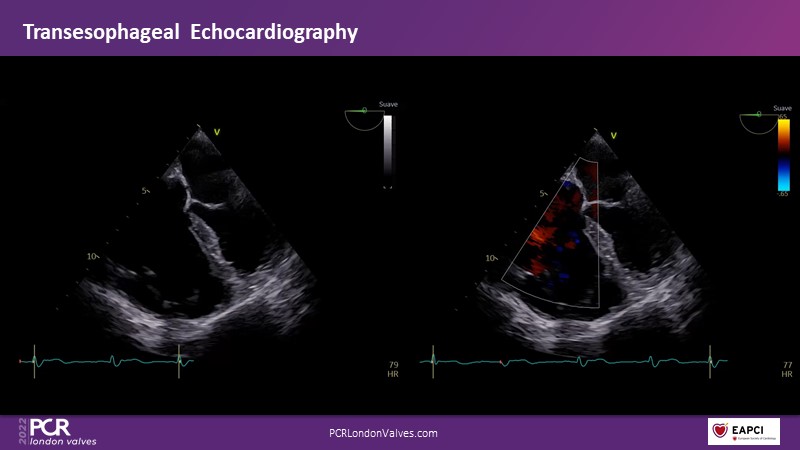

Watch this session if you want to learn tips and tricks that influence procedural strategy through a real-life case as well as anatomical factors that contribute to tricuspid valve complexity and choice of treatment, followed by the latest clinical data.

- To learn more about the anatomical factors that contribute to tricuspid valve complexity and choice of treatment

- To share tips and tricks that influence procedural strategy through a real-life case